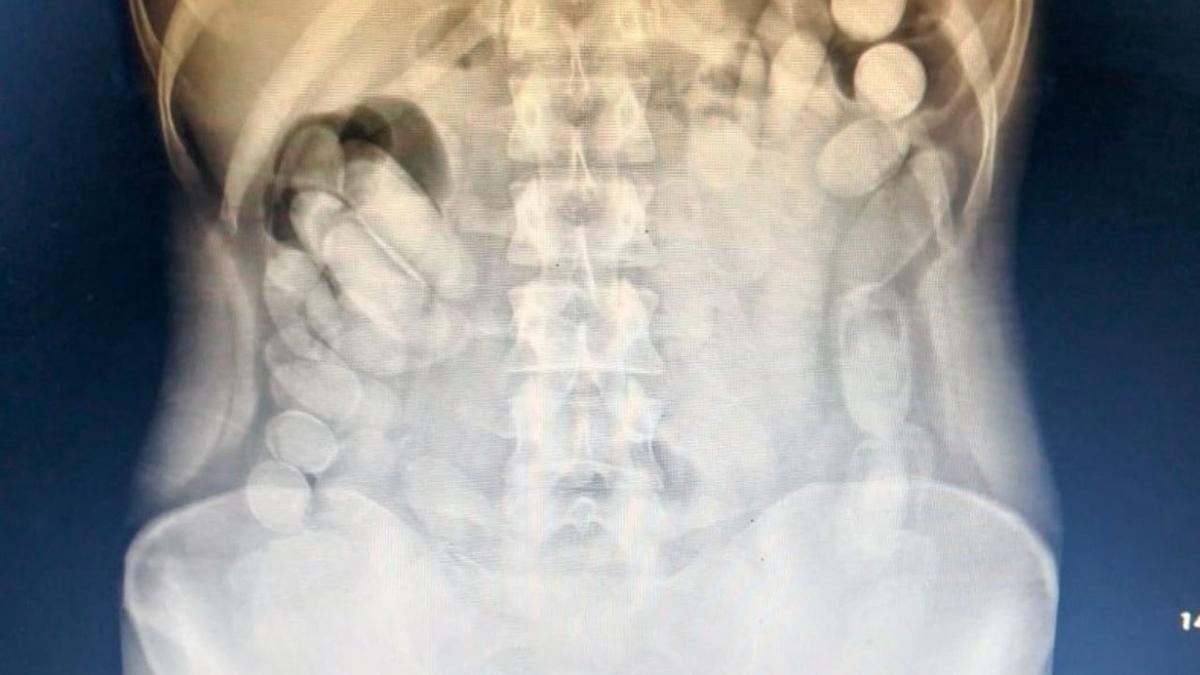

Al llegar al hospital, se le realizó una radiografía que confirmó la presencia de cápsulas en su abdomen. Posteriormente, evacuó un total de 106 cápsulas. Una vez sometidos los 118 envoltorios cilíndricos al Narcotest, el resultado fue positivo para cocaína, alcanzando un peso total de 1 kilo 388 gramos.